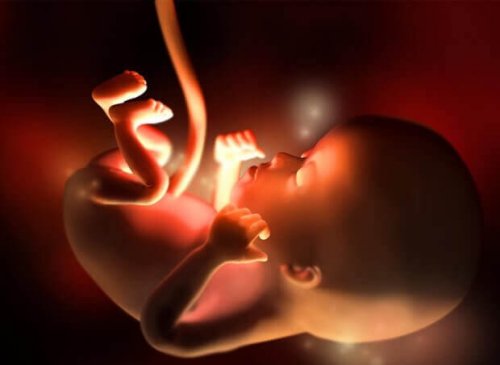

Au cours de la douzième semaine de la grossesse, le dernier du premier trimestre, votre bébé mesurera entre 5 et 6 centimètres et pèsera entre 8 et 14 grammes.

Son cœur bat très fort, à 160 battements par minute, et ses mouvements commencent à se multiplier, même s’ils sont encore imperceptibles pour vous.

Ses membres sont déjà formés, les organes commencent à mûrir rapidement et même ses intestins, jusqu’à présent reliés à la base du cordon ombilical, se déplacent vers la cavité abdominale.

De même, sa tête a déjà acquis sa forme arrondie. Sa bouche peut s’ouvrir et se fermer et ses oreilles sont à leur place. Les ongles commencent à être définis, ainsi que les cordes vocales.

Au cours de la douzième semaine de grossesse, les reins commencent à générer de petites quantités d’urine et même les premiers vestiges de poils sur le corps apparaissent.

Bien que le sexe du bébé ne puisse pas encore être différencié par échographie, l’appareil génital est en plein développement à ce stade. De plus, à cette “âge”, le bébé est déjà capable de bâiller, de hocher la tête et d’avaler.